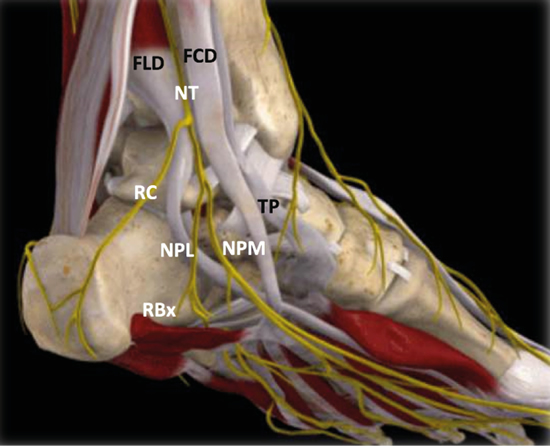

Figura 3. Túnel tibiotalocalcáneo. El nervio tibial (NT) se divide en la rama calcánea (RC), el nervio plantar medial (NPM) y el nervio plantar lateral (NPL) del que se escinde la rama de Baxter (RBx). Las estructuras musculotendinosas tibial posterior (TP), flexor largo del primer dedo (FLD) y flexor largo de los dedos (FCD) acompañan al nervio tibial en su recorrido por la cara medial del tobillo y el pie. Imagen modificada de la App Ankle & Foot Pro III.

Figura 5. Túnel tibiotalocalcáneo. La porción proximal o túnel tibiotalar superior en azul. Estructuras nerviosas: nervio tibial (NT), rama calcánea (RC), nervio plantar lateral (NPL), nervio plantar medial (NPM), rama de Baxter (RBx). Estructuras musculotendinosas: tibial posterior (TP), flexor largo del primer dedo (FLD) y flexor largo de los dedos (FCD). Imagen modificada de la App Ankle & Foot Pro III.

Figura 13. Línea de Dellon-Mackinnon (A-B) y triángulo de Heimkes (A-B-C). Se observan el nervio tibial (NT) y las ramas calcánea (RC), el nervio plantar lateral (NPL), el nervio plantar medial (NPM) y la rama de Baxter (RBx). Imagen modificada de la App Ankle & Foot Pro III.